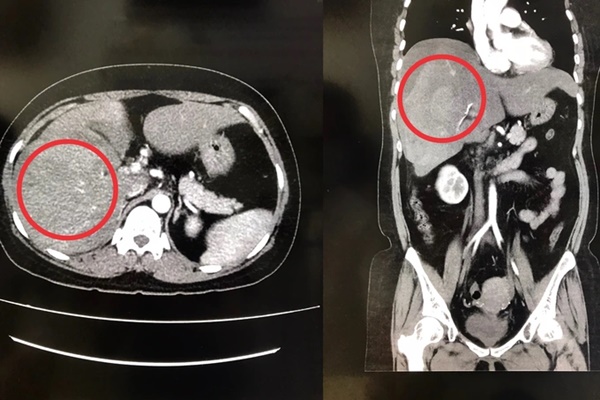

Mới đây, thông tin một phụ nữ đeo đai nịt bụng để giảm cân đến nỗi bị vỡ gan, xuất huyết nội chính là hồi chuông cảnh báo cho một trong những cách giảm cân độc hại này. Ngoài đeo đai nịt bụng còn có vô số những kiểu giảm cân chị em nên sớm tỉnh ngộ.